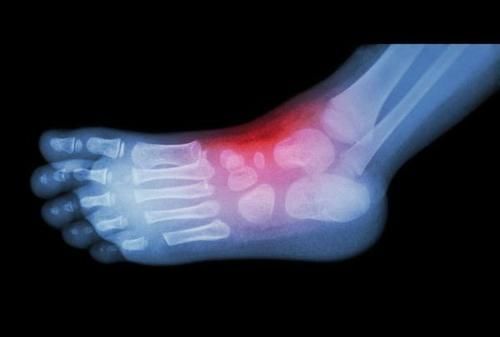

1、关节肿胀

关节部位肿胀是类风湿性关节炎引发的典型症状,这是因为关节部位出现了积液,除了肿胀之外,随着时间的推移,关节发炎,还有可能促使关节附近的皮肤发红。

造成这一结果的因素是流量患处的血流量增加,此时想要缓解,可以采用冰敷的方式,但只能治标不能治根。